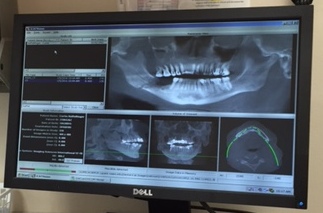

After visiting on Monday of this week with Team Marx associated with Jackson South Community Hospital, we had no doubt the Lord had led us to just the right resource to deal with my fractured mandible. The image above shows the results of a CT scan they did in the office that day. If you look closely at the largest of the pictures head on at the top, you can see to the left (my right side) the break in the bone. Apparently there are some splinters of the jaw floating around in there adding to my misery. To use one of the doctors words after they examined the area treated with radiation in 2005–“You got fried.” And so I did and these are some of the unfortunate consequences.